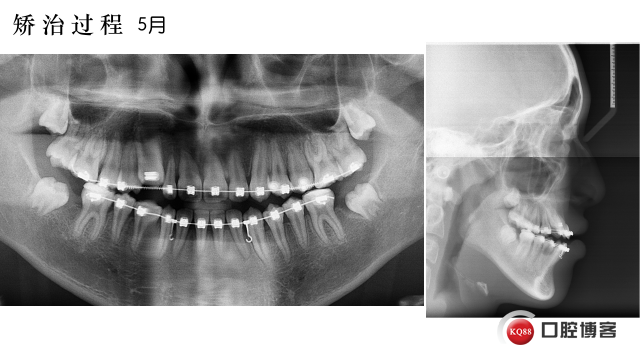

拔除37,47,全口固定矫正,使用低转矩DamonQ金属自锁托槽,粘接全口托槽

42.41.31.32倒粘(托槽转矩从-11度变成+11度)、通过配合Damon含铜镍钛弓丝扩大上颌牙弓,在13和25处放置推簧,待推出足够空间在将13,25纳入牙弓。下颌排齐后在外斜线处植入2*10mmVector支抗钉整体远移下牙弓,调整磨牙尖牙关系及覆合覆盖问题。要求患者进行舌肌锻炼。

要感谢林老师指出我这里的一个不足,下颌的牵引要用短牵引钩,长的不利于下颌平面的逆旋,长问号钩更适合整体平行远移下颌牙列!!